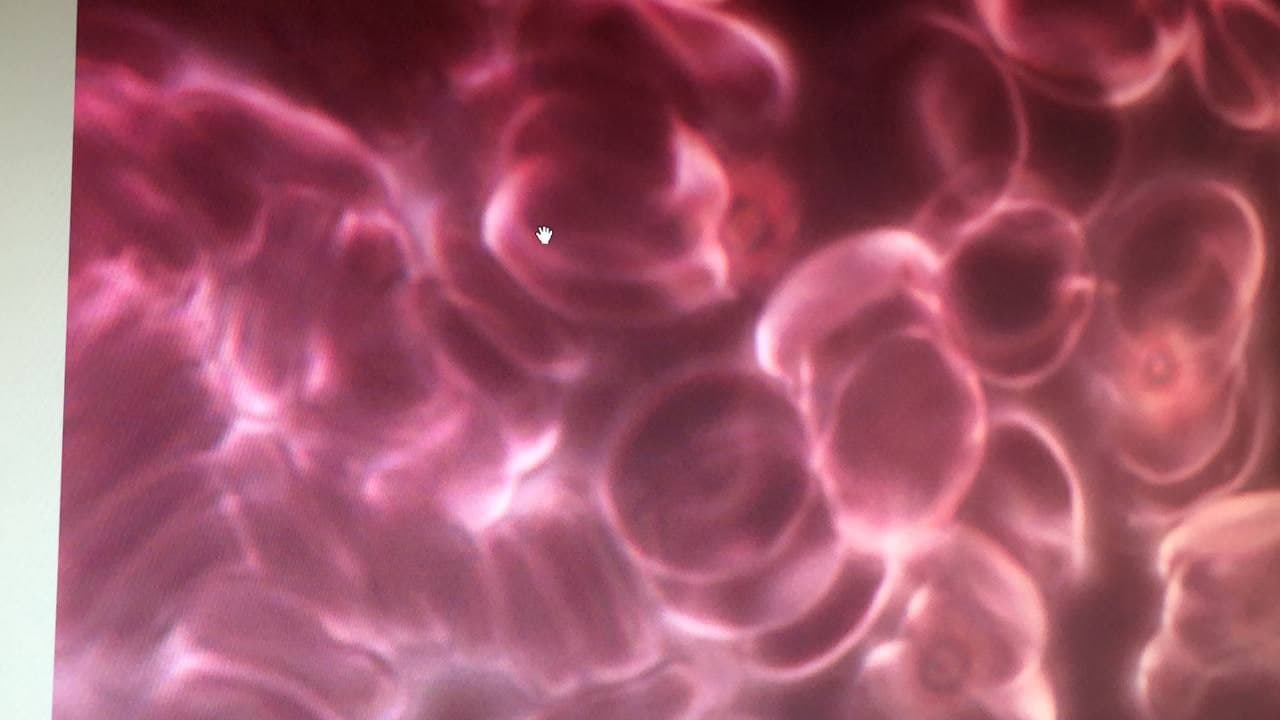

Beim gesunden Blut (links) sind die Blutzellen wie

Billardkugeln und der Sauerstofftransport ist 100%,

die Person ist sportlich fit. Link:

https://www.bitchute.com/video/DW5aZQCK8YBc/ - Die

Blutzellen der GENgeimpften sind zerknittert,

verhaken sich, provozieren Blutgerinnsel+Thrombosen.

UND: Sauerstofftransport ist kaum noch möglich,

Dauermüdigkeit, weil alle Organe unterversorgt sind.

With healthy blood (left) the blood cells are like

billard balls and there is full 100% oxygen

transport, so the person is sportive and fit. The

blood cells of GENE vaccinated are crumpled, they

stick together forming clots and thromboses. AND:

oxygen transport is hardly possibble, eternal

tiredness comes up because all organs suffer lack of

oxygen.

Bei den Ungeimpften haben die Blutkörperchen eine runde

und abgegrenzte Struktur, die je nach Lebensweise

Unterschiede aufzeigt.

Bei den Geimpften mit Biontech und Moderna sieht man im

Dunkelmikroskop, wie die Blutkörperchen zu einem

Breiartigen Cluster zusammen gepappt sind und fast keine

Beweglichkeit mehr zeigen. Die Aufnahme von Sauerstoff